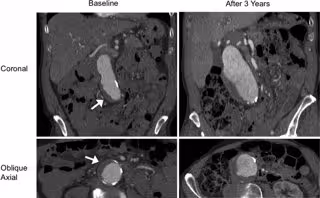

El doctor Zhu y sus colegas centraron su estudio en el trombo intraluminal, un coágulo de sangre en la pared de la aorta en la ubicación del aneurisma. Los trombos intraluminales están presentes en la mayoría de los aneurismas cerca del umbral de reparación de 5,5 cm, y en un número considerable de aneurismas más pequeños.

Los investigadores utilizaron imágenes transversales de alta resolución con tomografía computarizada o resonancia magnética para evaluar a 225 hombres con aneurisma aórtico abdominal. El seguimiento duró, en promedio, más de 3 años.

Algo más de la mitad de los pacientes tenía un trombo intraluminal. Los aneurismas de aquellos con trombo intraluminal fueron mayores al inicio y crecieron a una tasa de 2 milímetros por año, el doble de rápido que la tasa de crecimiento de 1 mm por año en personas sin trombo intraluminal.